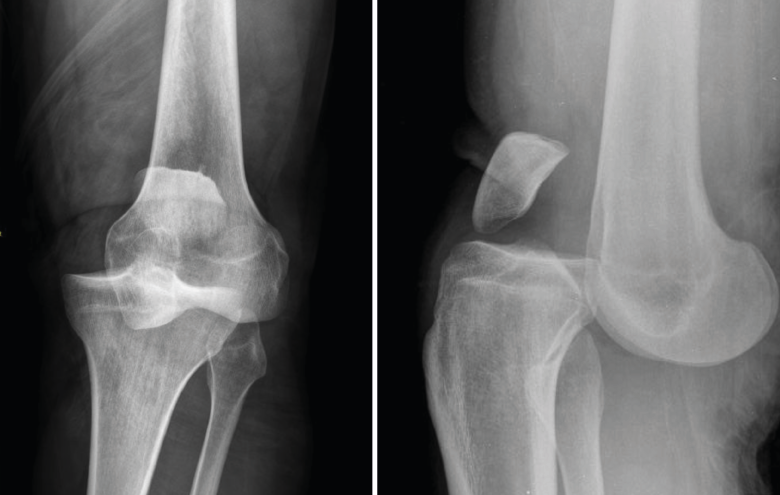

3. Artrosis

La gonartrosis es la causa más frecuente del dolor de rodilla después de los 50 años. En la radiografía se observa una reducción de la interlínea femorotibial o femoropatelar, y una osteofitosis marginal (Figura 6).

Figura 6. Radiografías anteroposterior y lateral de rodilla: osteofitos en compartimentos femorotibial y femoropatelar.